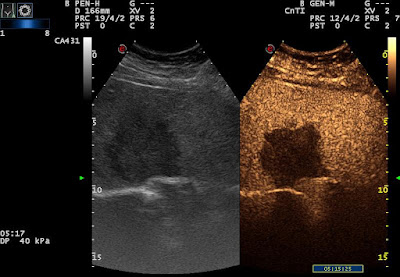

Hepatic metastasis of ovarian cancer – CEUS Szerző: admin | szept 8, 2011 | CEUS, Focal liver lesions | Nincsenek hozzászólások arterial phase – rim enhancement (poorly detectable) wash out total wash out lesion 3087332011.07.12.